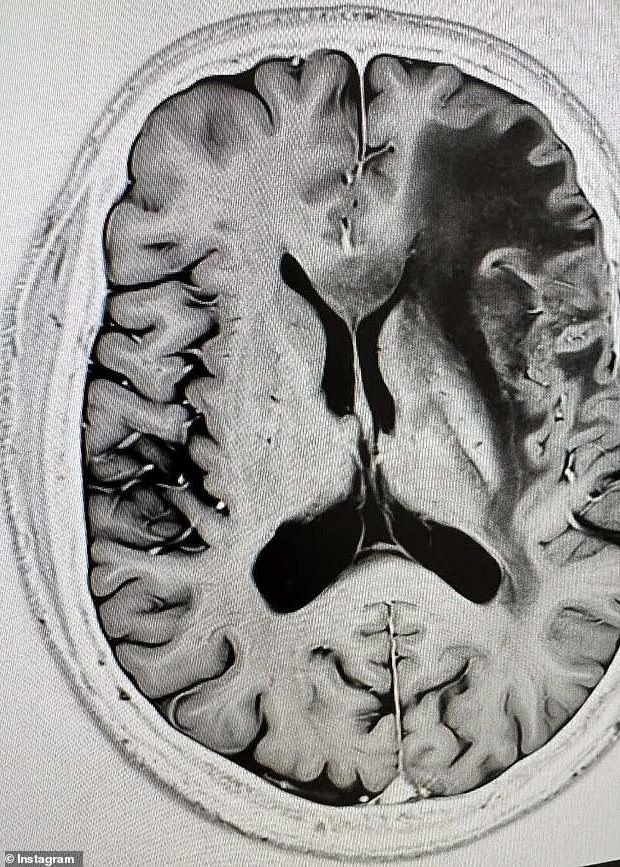

On Monday, Prof Scolyer revealed the glioblastoma in the left side of his brain had progressed as he shared the results of a recent MRI on his Instagram .

He noted, 'A recent MRI revealed additional progression of my glioblastoma (IDH wild-type) on the left side of my brain along with nearby areas showing reactive changes.'